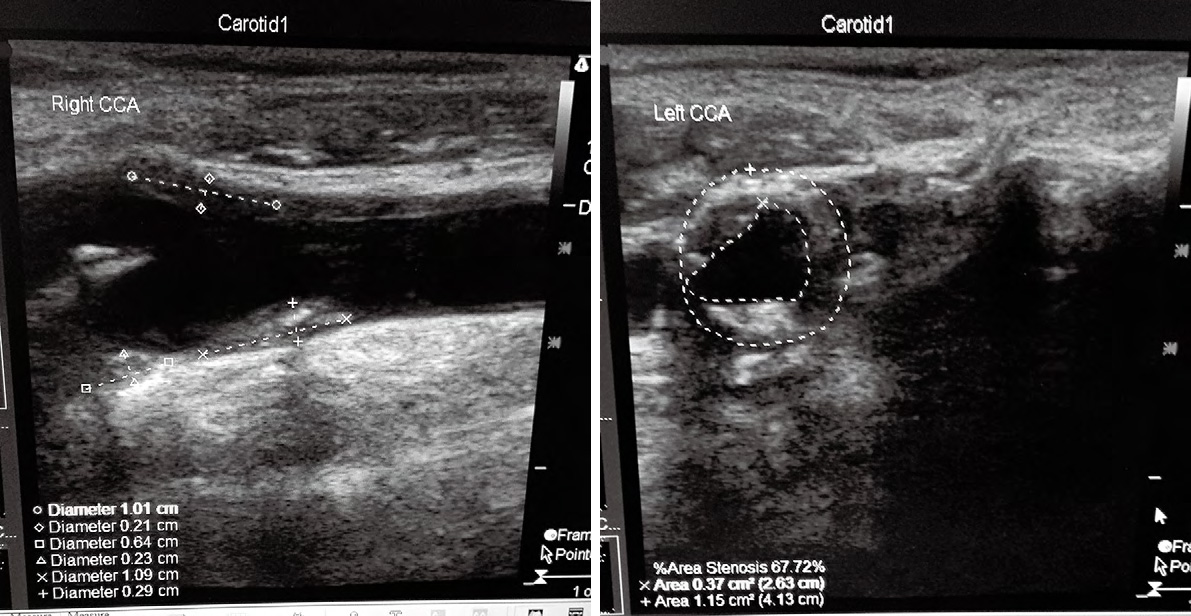

1、2114例患者中的典型病,老年男,主訴為頭昏伴雙手麻木不適數(shù),加重1周來我院神經(jīng)科門診就,TCD和頸動脈超聲聯(lián)合檢查進行早期篩查。檢查結(jié)果如下:

1TCD示:雙側(cè)頸內(nèi)動脈末-大腦中動脈流速顯著增快,伴頻譜紊亂渦流形成, 考慮雙側(cè)頸內(nèi)動脈末-大腦中動脈狹窄;壓頸試驗后證實右側(cè)大腦前動脈、雙側(cè)大腦后動脈代償;腦血管彈性減退

2 頸動脈超聲提示:雙側(cè)頸動脈及椎動脈硬化;雙側(cè)頸部數(shù)個多發(fā)性動脈粥樣硬化斑塊形成;右側(cè)頸總動脈球部斑塊處管腔輕度狹窄;左側(cè)頸總動脈球部斑塊處管腔中度狹窄